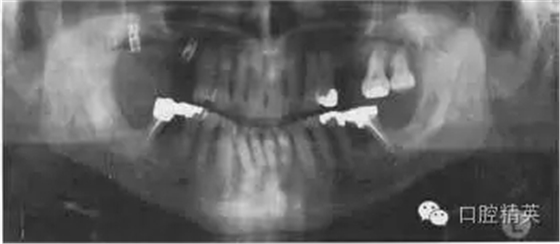

圖38.2 患者牙齒的全口牙位曲面體層X線片

牙齒全口牙位曲面體層X線片如圖38.2所示,你看到了什么?

答:全口牙位曲面體層X線片不是很清晰?;颊哳^位沒擺正,使圖像產(chǎn)生很大扭曲。下頜骨下緣呈彎曲圖像,且下前牙被縮短了。因?yàn)轶w位不正,脊柱陰影也被增強(qiáng)了。因?yàn)橛跋裰丿B,中線處的牙齒沒在中點(diǎn)。頭偏向一邊,一側(cè)影像被放大。這在后牙牙冠上很容易看出來,因?yàn)橛覀?cè)比左側(cè)的牙冠大?;颊叩男g(shù)后片如圖38.3,它顯示了正常片子應(yīng)顯示的樣子。

X線片顯示,了右下及左下第二磨牙周圍廣泛的骨質(zhì)破壞。左下第二磨牙有骨喪失并有根分叉處齲壞。下頜兩個(gè)第一磨牙有明顯的根分叉病變,但卻不松動(dòng)。

種植體在哪里?你怎樣更準(zhǔn)確的確定它們的位置?

全口牙位曲面體層X線片不足以準(zhǔn)確定位種植體的位置。它們出現(xiàn)在焦點(diǎn)上,因?yàn)槟パ绤^(qū)的焦槽非常寬,以至于并不能為其頰舌向位置提供線索。它們的位置和角度對于決定這些種植體能否支持修復(fù)體有重要作用。

如果種植體的末端不能在口內(nèi)確定,那么就只能通過CT掃描或多向體層攝影術(shù)等體層攝影術(shù)來進(jìn)行準(zhǔn)確定位。常規(guī)的CT掃描費(fèi)用高,并且要求特殊軟件來預(yù)防偽影。利用設(shè)備Scanora或Tomax采用多向體層攝影術(shù)(螺旋或外擺線)非常容易得到頜骨任何部位的斷層影像,并且這一技術(shù)和錐形束CT技術(shù)是最好的方法。如果種植體位置不當(dāng),可以在牙槽嵴上放置不透射的標(biāo)記物幫助定位后,再行拍攝X線片,或者假設(shè)種植體處于恰當(dāng)?shù)奈恢茫涂梢苑_瓣膜了。

種植體的位置不是很好,即使在全口牙位曲面體層X線片上就能看到種植體間不平行,從而不利于固定修復(fù)。種植體很小,類型不同、已有部分骨整合。近中的種植體支持骨較少,是否能承擔(dān)較大[he]力不清楚。